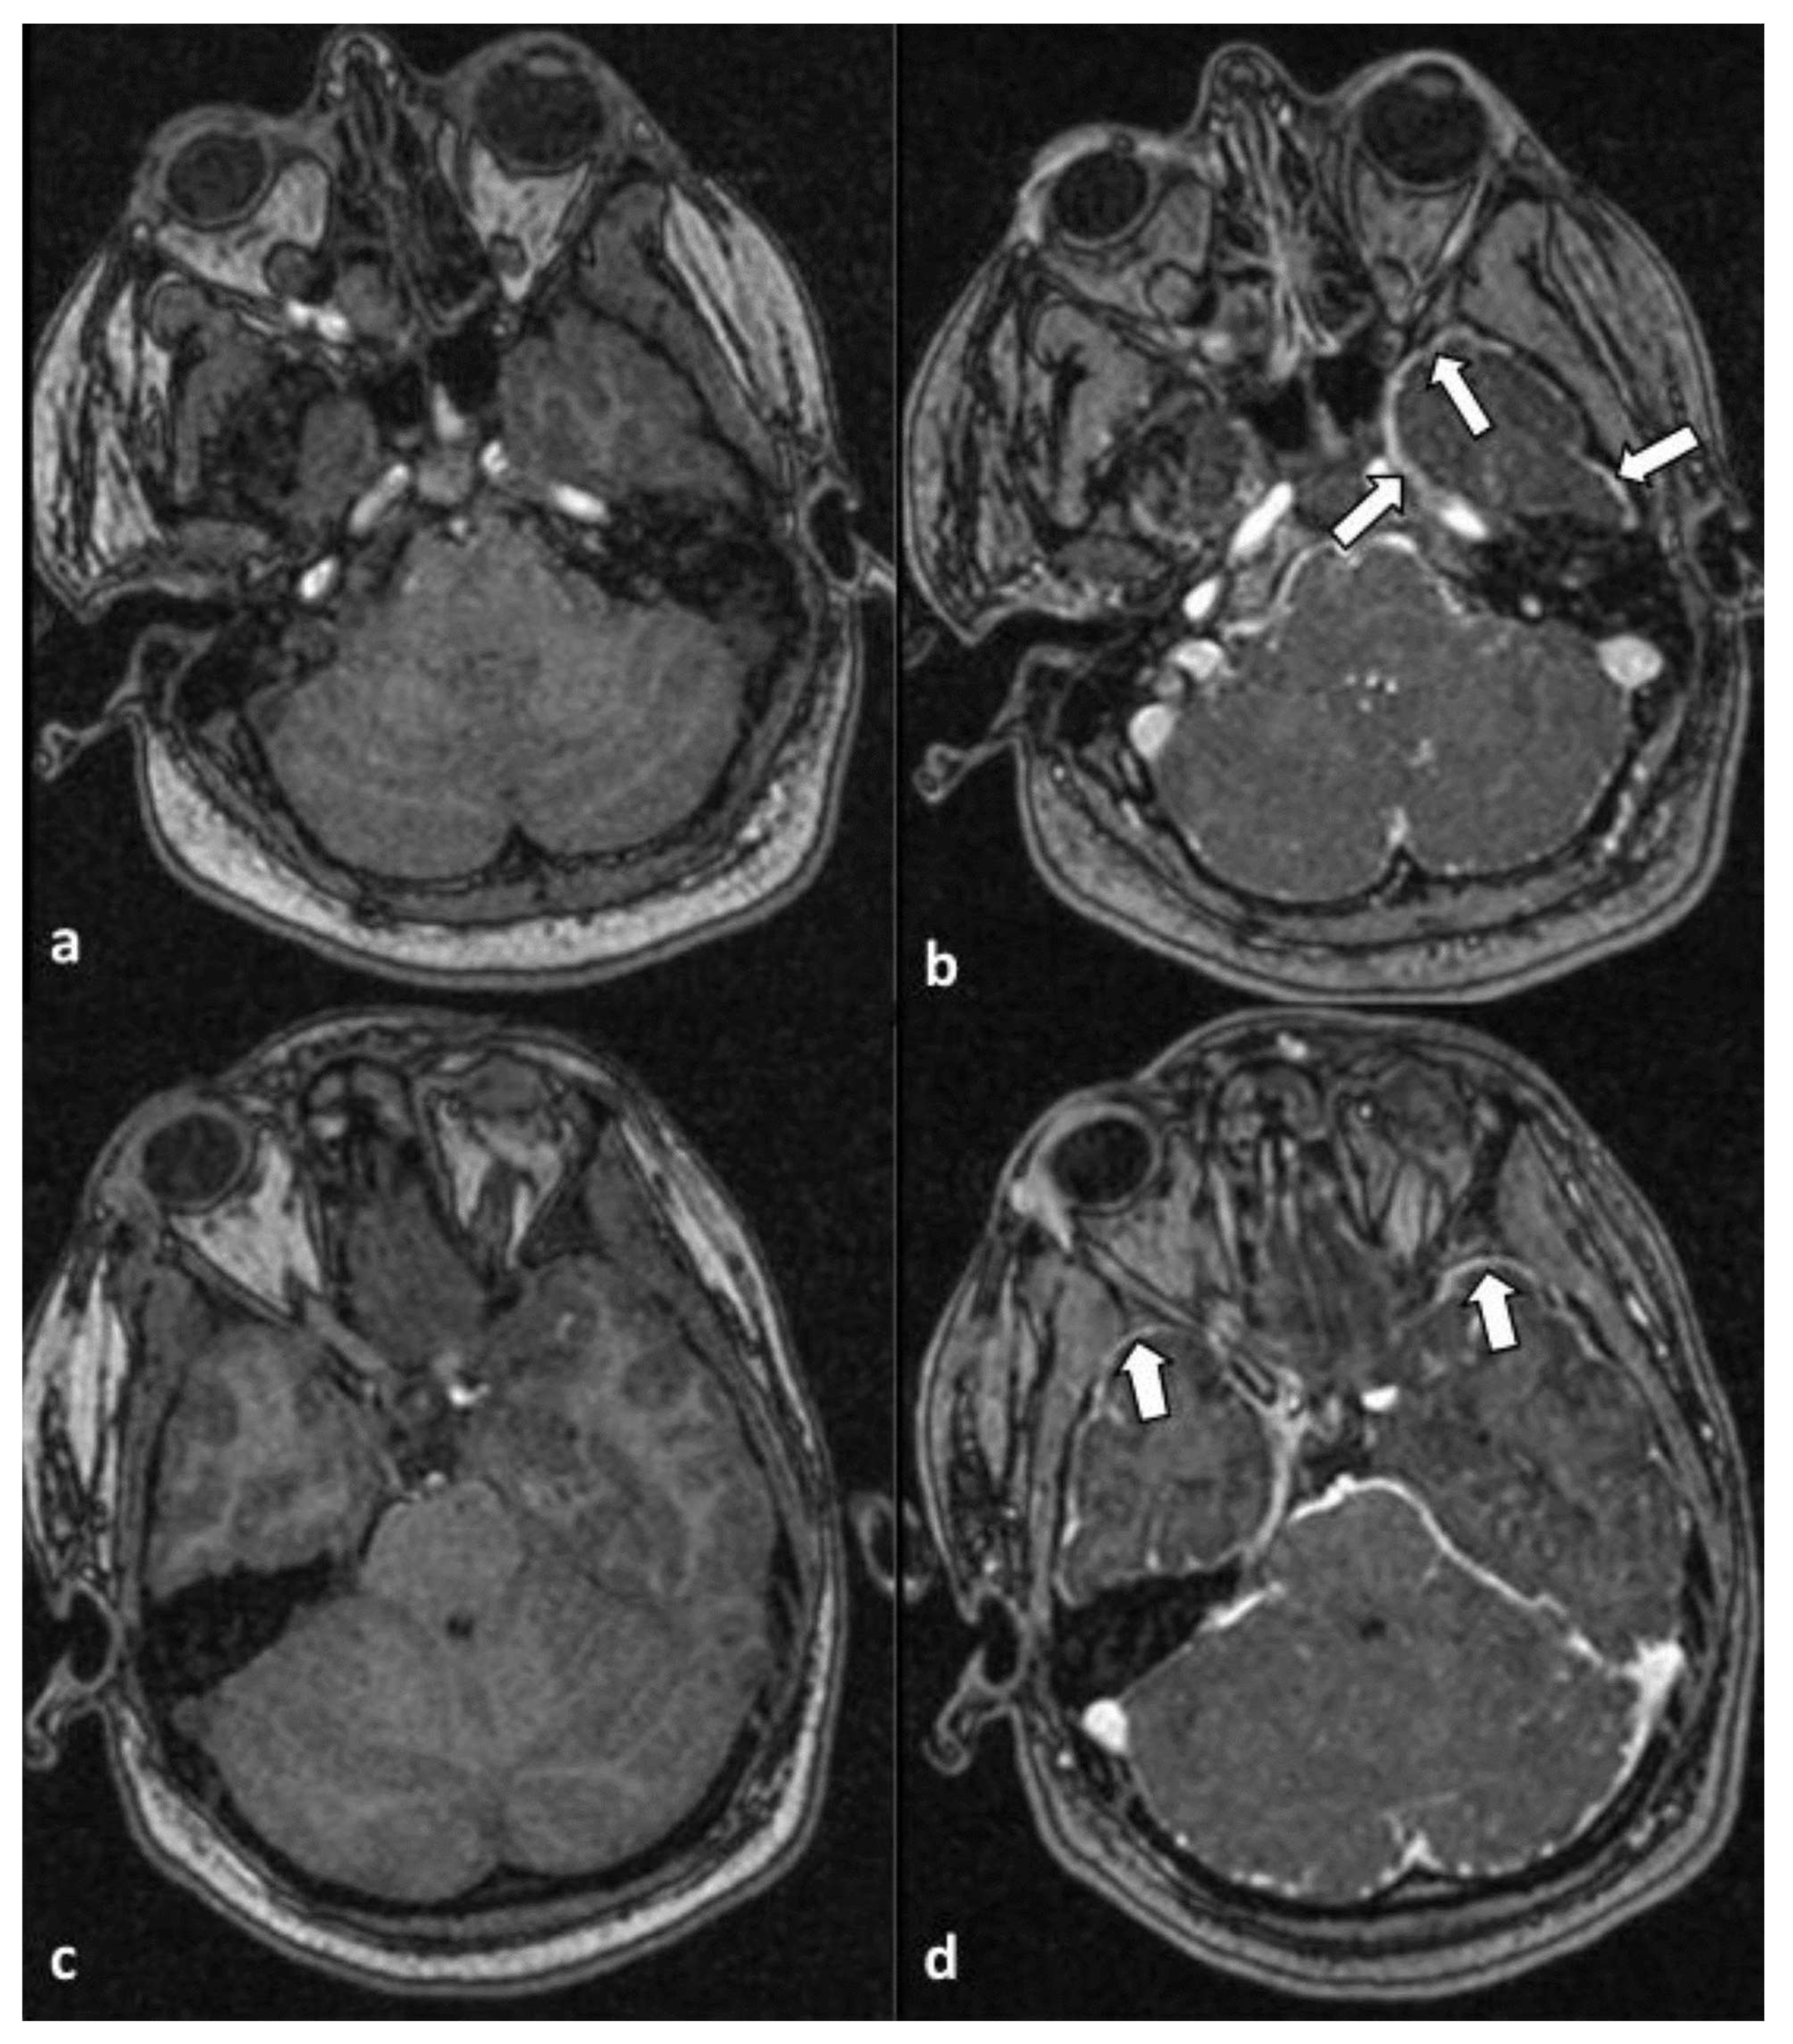

A habit history of frequent spring water consumption reported by her closest contact, along with the reports of endemic tropical diseases on the island of her residency, raised the suspicion of leptospirosis infection, although the serological test of the first sample was negative. Based on that, eight days later, a second blood sample revealed positive IgM against Leptospira (immunochromatographic assay) and confirmed the diagnosis. Targeted therapy with 2 g of ceftriaxone intravenously, which was started empirically on the second day based on high grade of clinical suspicion was completed. On the 5th day, an attempt of analgosedation discontinuation was interrupted as the patient presented multiple episodes of myoclonus, exophoria, and impaired level of consciousness (GCS 6/15). A brain magnetic resonance imaging (MRI) revealed findings indicative of cytotoxic edema in the context of global hypoxic ischemic injury (Figure 1) of the caudate (white asterisk) and the lentiform (black asterisk) nuclei, bilaterally. On the corresponding apparent diffusion coefficient map (d), the same areas appeared hypointense.

Figure 1. Axial diffusion-weighted imaging (a) and apparent diffusion coefficient map (b) at the level of the convexity, showing increased and decreased signal intensity of the cerebral cortex along both frontal lobes (arrows), respectively. Axial diffusion-weighted imaging (c) at the level of basal ganglia reveals symmetrical hyperintensity of the caudate (white asterisk) and lentiform (black asterisk) nuclei, bilaterally. On the corresponding apparent diffusion coefficient map (d), the same areas appear hypointense.